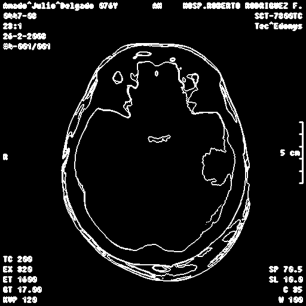

An example of an applications of our proposed strategy to a medical image is shown in Figure 7. In this case, we used different values of and in the . This is a preliminary result. A deeper paper about these results will be published.